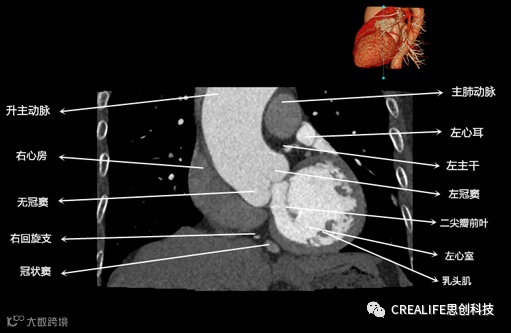

今天,跟大家分享心脏影像的经典层面——冠状位。通过冠状位的影像,我们可以从正位观察到心脏结构,看到主动脉的纵向剖面及冠窦交界处的心脏形态等多方位的心脏结构。现在,就让我们率先一睹“冠状位”的奇妙风采吧!

毋庸置疑,影像解剖学可为医师提供优良的诊断依据,包括瓣膜钙化程度、主动脉瓣环直径、主动脉窦直径及高度、冠状动脉开口高度、入径血管直径等关键数据,以此,为术前提供更全面的评估指标。